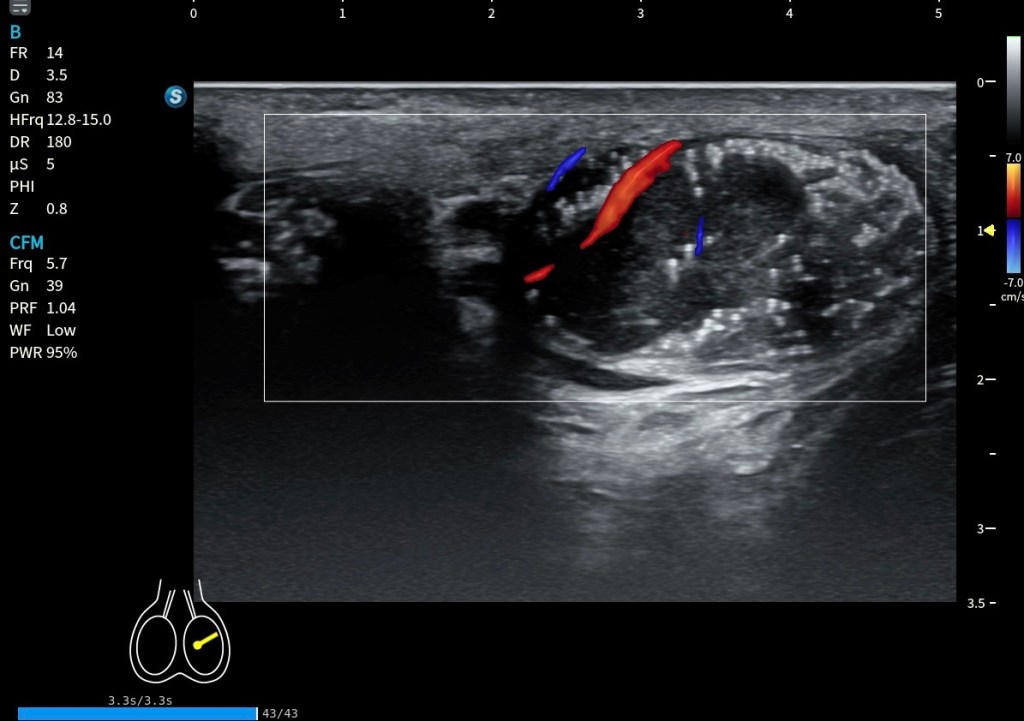

Un aspecto especialmente útil para su reconocimiento es su comportamiento dinámico. En el caso que da soporte a este post, al solicitar la contracción al paciente, se observa que las fibras laterales tienden a engrosarse, mientras que las fibras mediales se aplanan.

Desde el punto de vista clínico, el Platisma tiene un papel clave como referencia anatómica. Una identificación incorrecta puede llevar a errores en la localización del plano superficial, a una interpretación inadecuada de la profundidad de lesiones y a posibles fallos en procedimientos ecoguiados. Siempre identicar bien, región lateral y medial, estudiar en relajación y usar siempre estudio comparativo.

La alteración más habitual no es su ausencia, sino su cambio estructural con la edad. Las conocidas bandas platismales representan la manifestación clínica más frecuente. Estudios ecográficos han demostrado que estas bandas corresponden a un comportamiento dinámico real del músculo: durante la contracción, el grosor del platisma aumenta significativamente dentro de la banda (≈37,9%), mientras que en las zonas adyacentes puede incluso disminuir (≈20,3%) (Van der Lei et al., 2023). Esto refuerza la idea de que no se trata solo de un fenómeno estético, sino de una reorganización funcional del músculo y su interacción con la piel y la fascia.